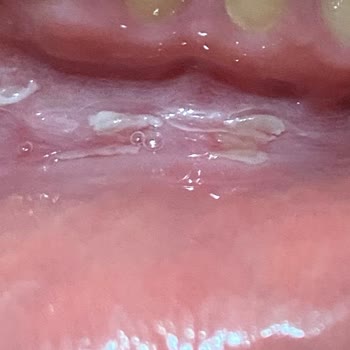

Parodontax diş macunu Parodontax diş Eti & hassasiyet macunu aldım. Diş macunu ağzımda aft yaptı. Ağzımın içinde yaralar var. Diş sağlığım tehlikeye girdi. 5 gündür Ağzımın içi yarı dolu ve yemeklerde zorlanıyorum. Bu konu hakkında çok mağdurum. Bu diş macunu markası için mutlaka inceleme yapılmalı...